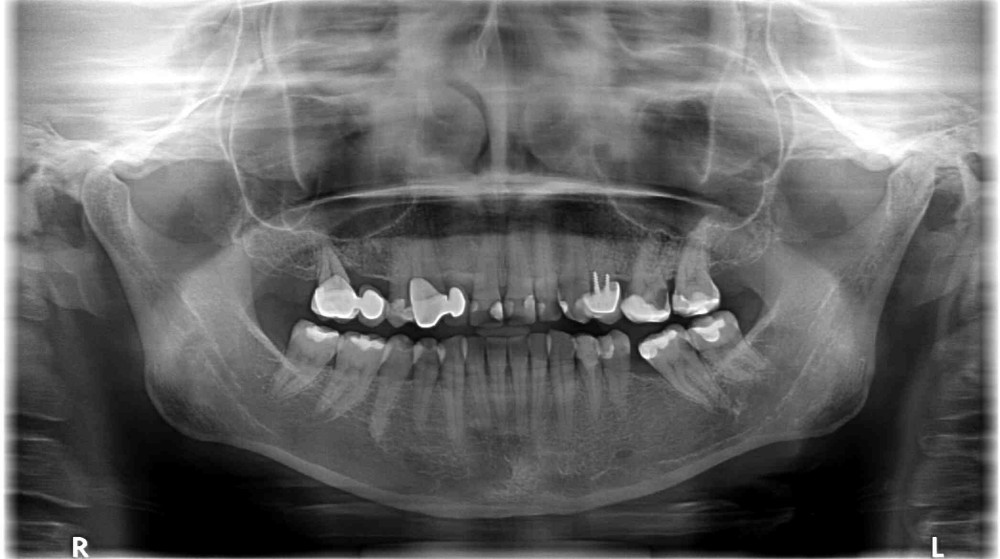

Dokumentacja RTG

- OPG przed zabiegiem wykonane przez lekarza prowadzącego